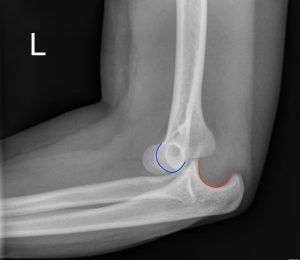

Posterior Elbow Dislocation, Lateral XRay, dislocated, Annotated. JETem 2016